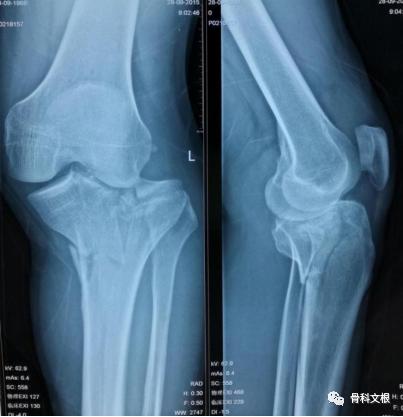

刘先生今年47岁,4个月前因外伤致左膝关节骨折,被紧急送往当地医院救治,入院影像学检查,诊断为:胫骨平台双髁骨折,Schatzker 分型为V型,伴不同程度的关节面塌陷和移位。

当地医院行复位内固定,术后4个月复查,胫骨平台骨折后畸形愈合,膝关节力线不良,左膝内翻畸形,行走障碍。

(矫正前)